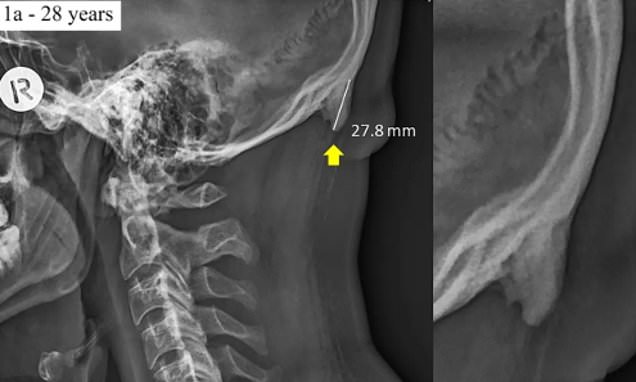

Αυστραλοί ερευνητές πραγματοποιήσαν την περίεργη ανακάλυψη εξετάζοντας εκατοντάδες X-rays ατόμων ηλικίας μεταξύ 18 και 30 ετών, διαπιστώνοντας ότι σχεδόν οι μισοί είχαν αναπτύξει επιπλέον οστό ή και οστά. Θυμίζουν τα οστά που συνήθως παρατηρούνται σε ηλικιωμένους ανθρώπους που το σώμα τους έχει υποστεί μακροχρόνια κακή στάση και σημαντικά φορτία στρες στα οστά τους.

Ο Δρ Shahar δήλωσε ότι η μελέτη εξέτασε 218 X-ray images(ακτινογραφίες) ατόμων ηλικίας μεταξύ 18 και 30 ετών, τις συσχέτισε με τη χρήση κινητών και διαπίστωσε ότι. Στους χρήστες κινητών ή tablets

- Το 41% είχε αναπτύξει μια οστεώδη κόκαλο στο πίσω μέρος των κεφαλών τους και κυμαινόταν σε μέγεθος από 10 χιλιοστά έως 30 χιλιοστά.

- Στις περισσότερες περιπτώσεις, τα οσφυϊκά στρώματα μετρούν λίγα χιλιοστά μόνο και παρόλα αυτά βρήκαμε προβολές από 10 έως 30 χιλιοστά στον υπό μελέτη νεαρό πληθυσμό.»